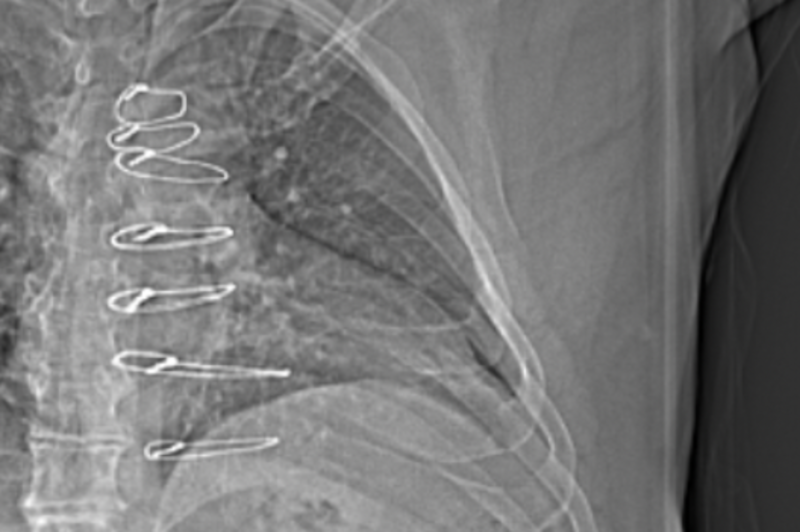

The results from my April 4, 2024, chest x-ray looked good. I still find it strange to view my x-rays and see some of the hardware that was left inside me after my April 27, 2023, septal myectomy (open-heart surgery) for Hypertrophic Cardiomyopathy. The notes above mention "Median sternotomy wires present," plus I also have retained epicardial pacing wires left inside me, which I have seen in other x-rays.

If you look very closely at the x-ray photo at the top of this blog post, and the following two x-ray photos, you can see the sternotomy wires:

As my appointment with Dr. Abu-Omar proceeded, I learned that my assumption about the appointment was completely wrong. I learned that while it is very rare, chest pain like mine can sometimes be caused by the sternal wires that were left in my body after the surgery. (To the right I added for a second time the same X-ray photo from April 4, 2024, that clearly shows the median sternal wires, and a close-up photo taken from the June 6, 2024, CAT Scan.)